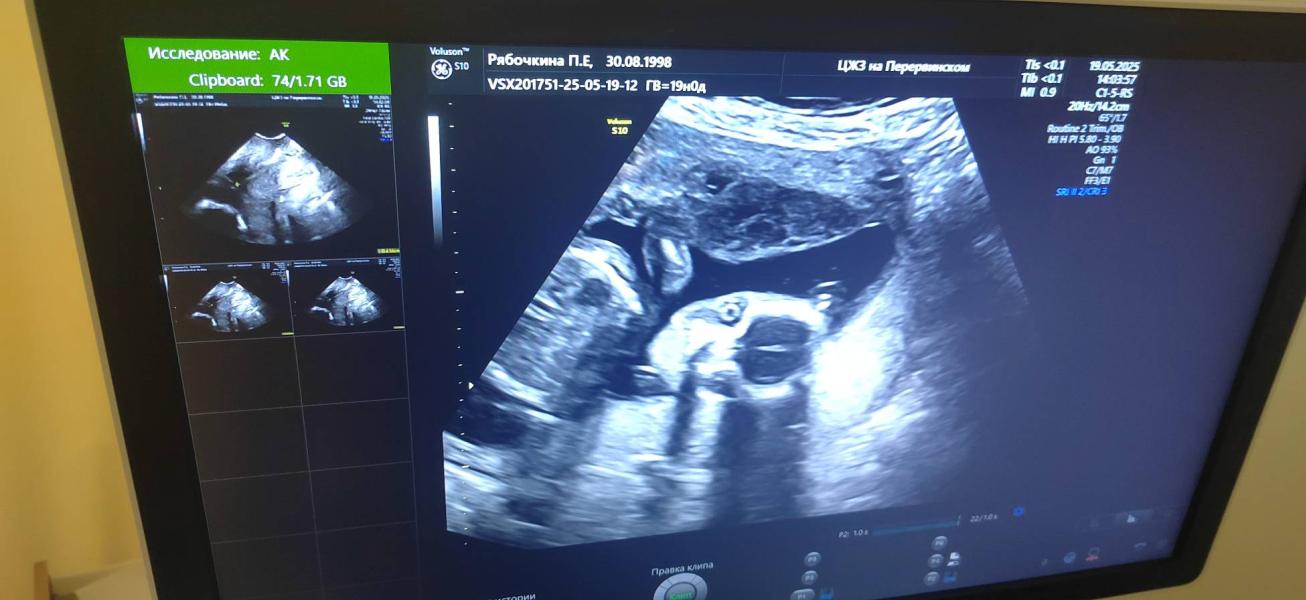

Как думаете тут понятно какого пола ребенок?

@polina.bolt666 голова справа, там видно мозг и глазик, слева животик и вроде чутка рука.

Девочка